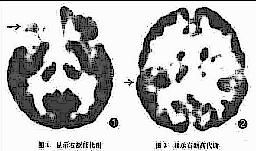

1.CT

大多有不同程度的皮質萎縮,部分出現左額葉低密度影、中線結構左移,腦室擴張等。